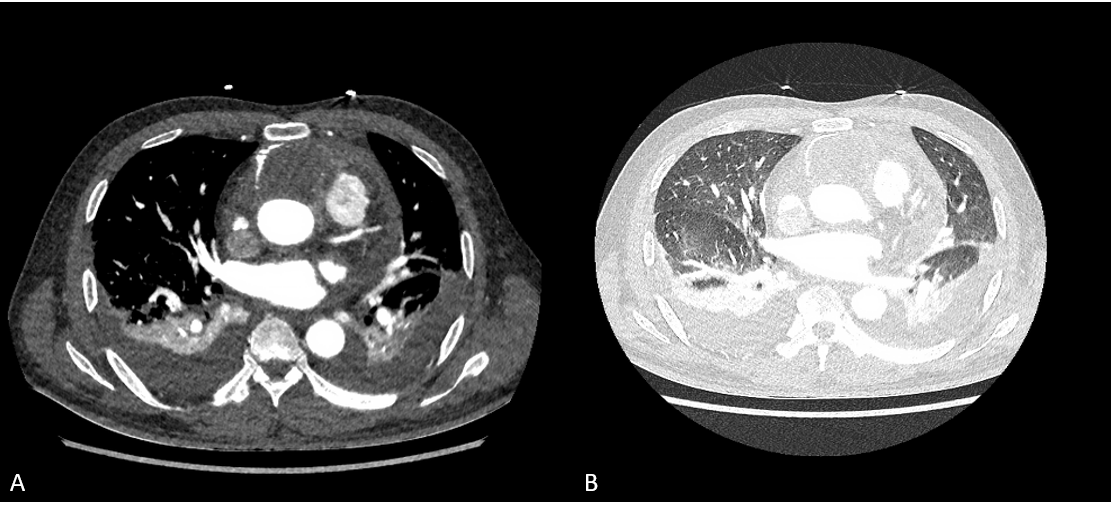

Figure 2. Tissue characterisation of the tumour. A. Cine SSFP (T2/T1 weighted image). B. T1-weighted sequence. C. T2-weighted sequence. D. STIR sequence. E. Native T1 map. F. T2 map. G. Early Gadolinium enhancement. H/I. Late Gadolinium enhancement (Magnetisation/PSIR).